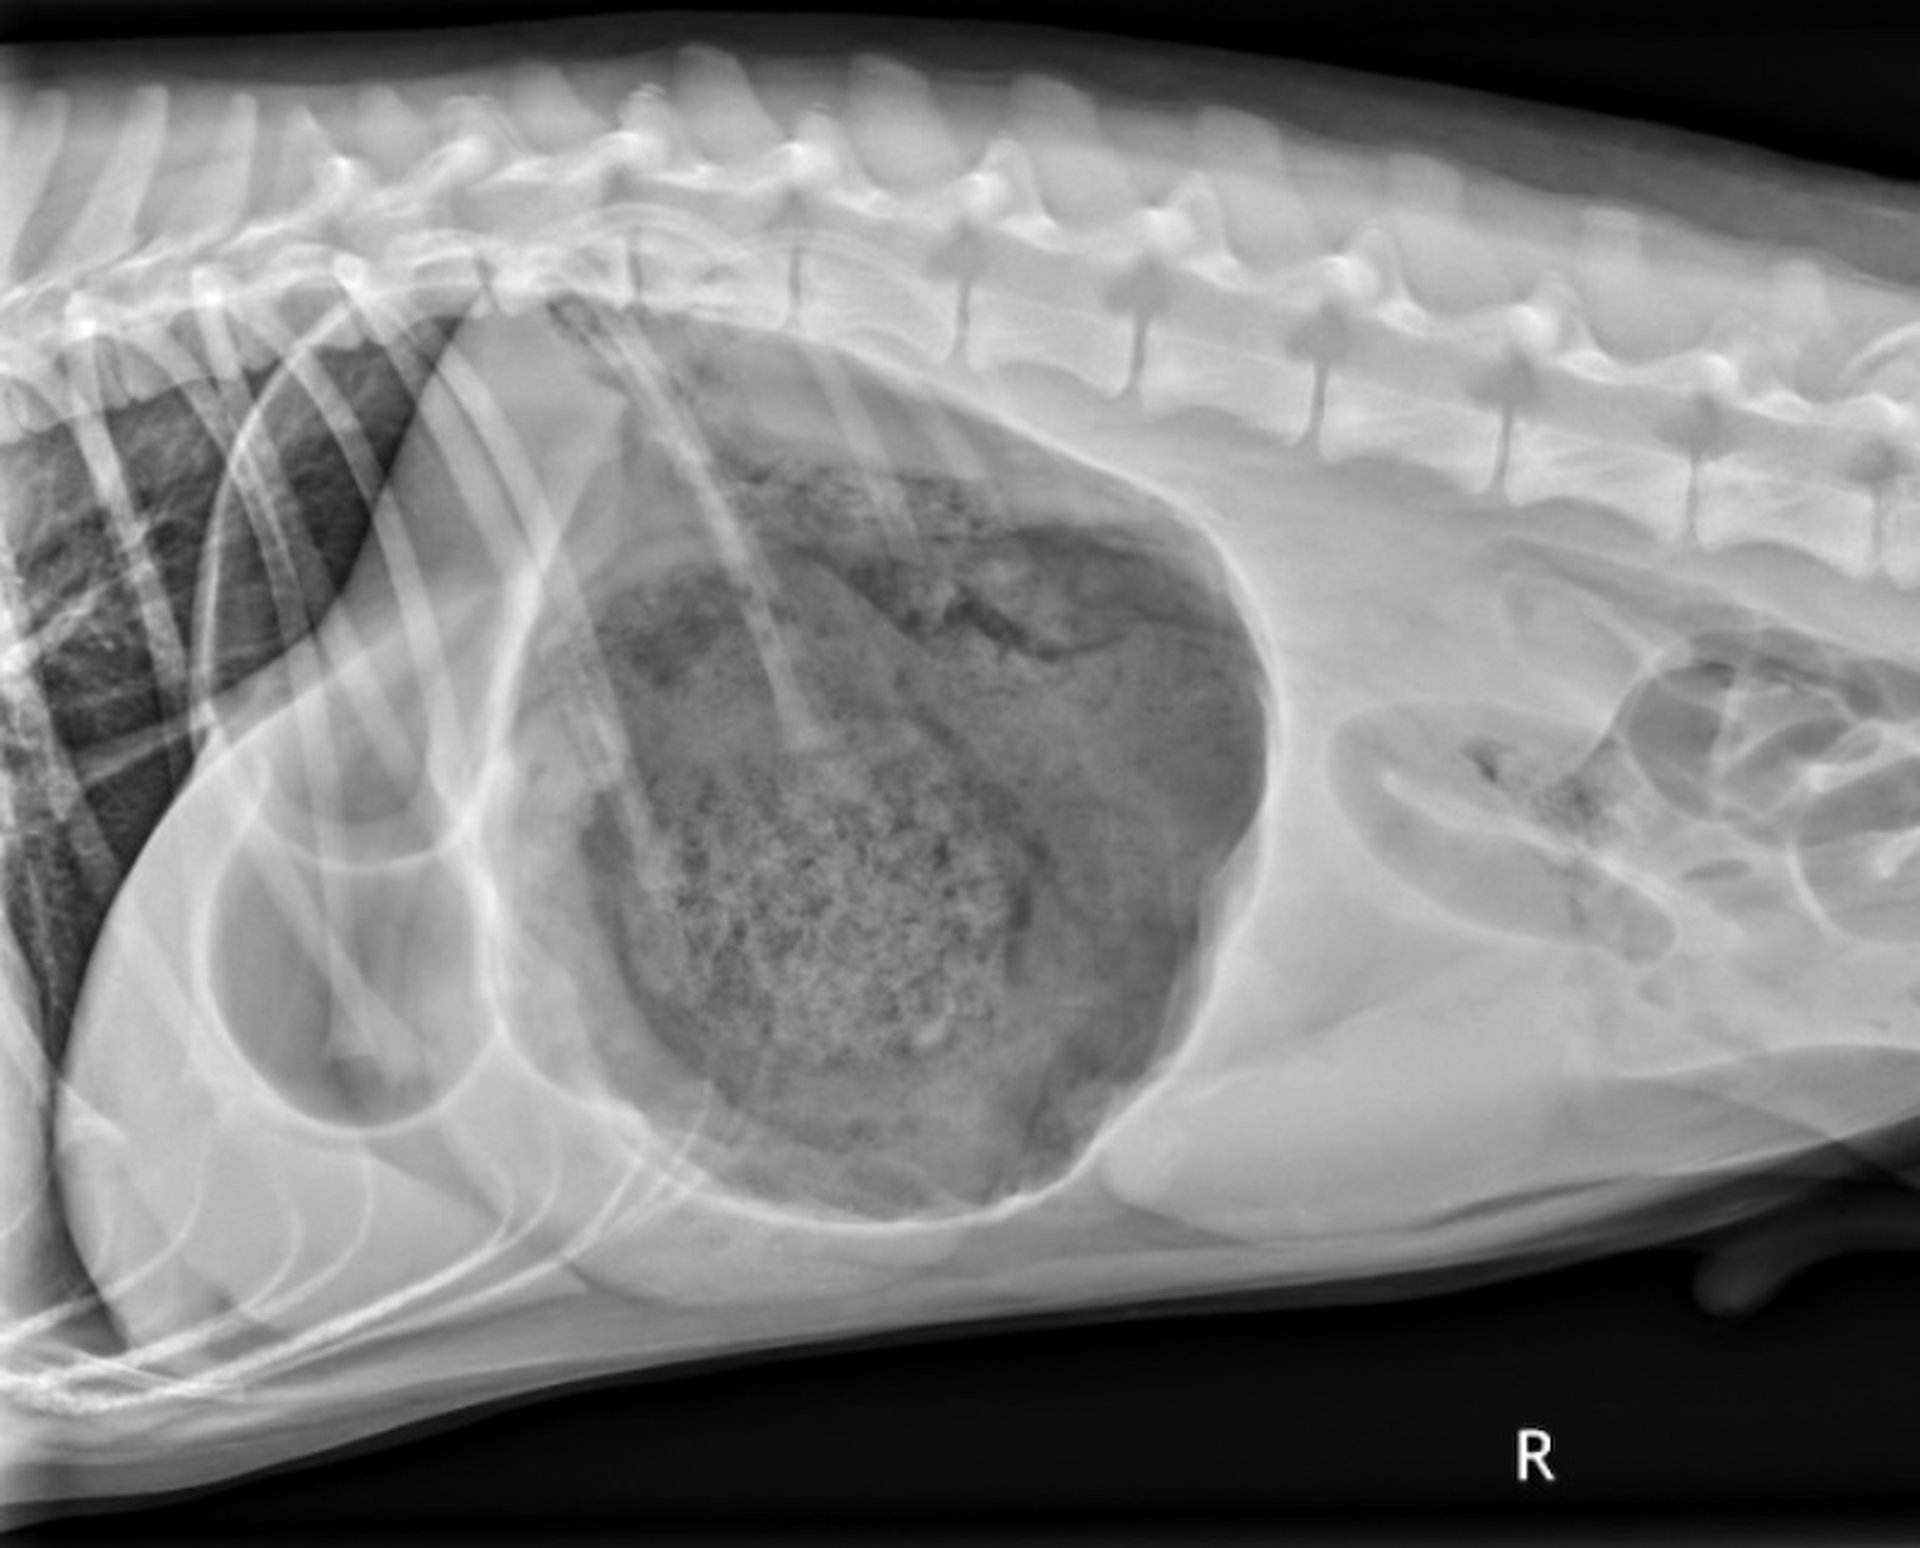

Lateral radiograph showing the "double bubble" in an 18-month-old Standard Poodle with gastric dilation and volvulus.

Courtesy of Dr. Kevin Winkler.